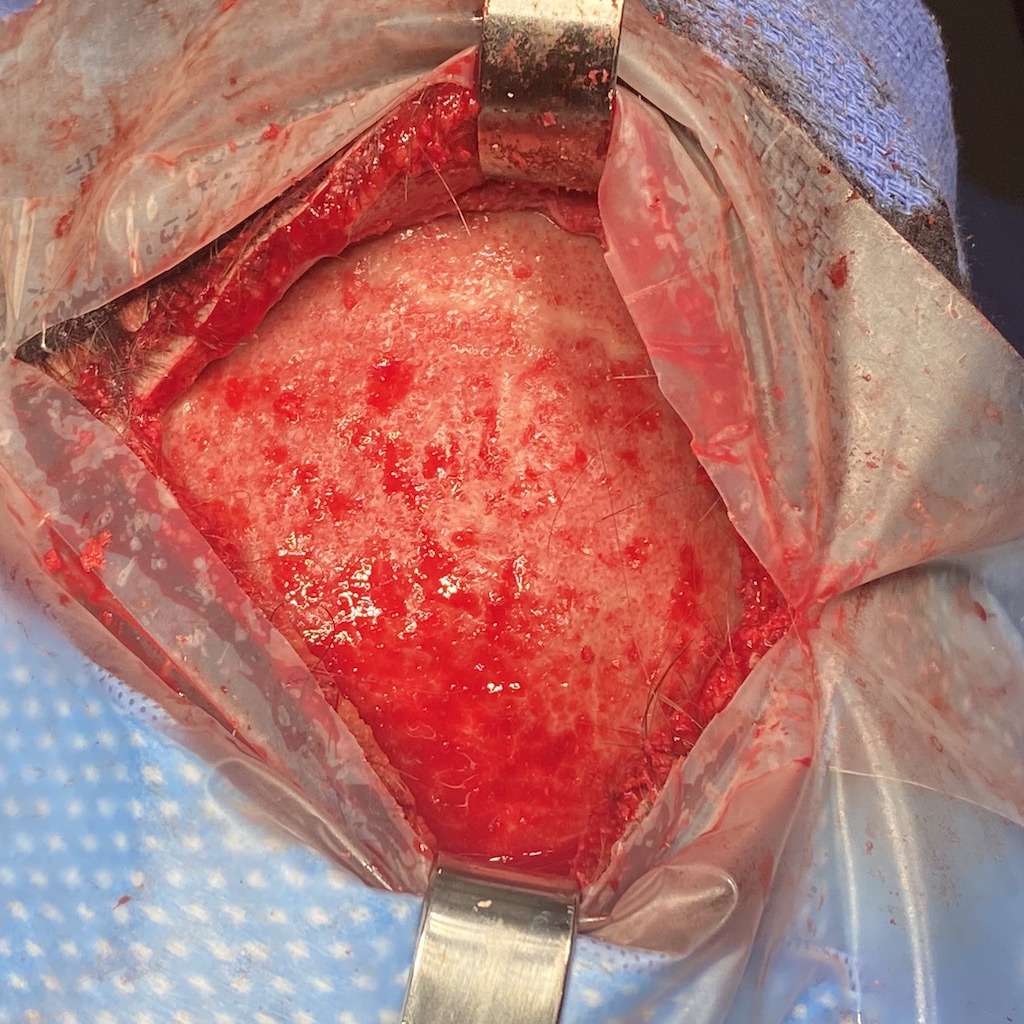

Desire for reduction of prominent occipital knob deformity.

Intraoperative result from occipital knob skull reduction through a direct small scalp incision.

Desire for reduction of prominent occipital knob deformity.

Intraoperative result from occipital knob skull reduction through a direct small scalp incision.